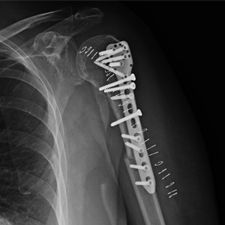

Ms. Q, age 74, initially presented on December 10, 2009, following a multiply comminuted, osteoporotic fracture of her left proximal Humerus. The decision was made to do an ORIF, which was carried out on December 14, 2009. She had a locking plate implanted following which she developed an infection of the wound. She was initially treated with antibiotics for this and she continued to get some oozing of the wound, which did not settle down despite continued use of the various antibiotics including Augmentin. Multiple wound swabs were done which failed to grow any organisms. The oozing persisted until about eight weeks following her operation when it finally settled down and the scar was noted to be tethered and was thought to be tethered onto bone.

She continued to have problems with intermittent cellulitis and pain in the arm and the decision was made to do an early removal of the metal work. This was carried out in mid March 2010 and at operation, which was done through the original incision and anterior extended deltopectoral approach, she was noted to have healed the fracture. She did well postop and was continuing to mobilize.